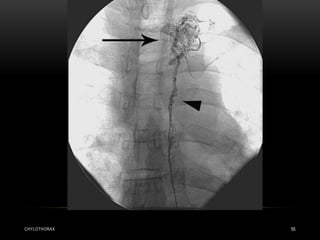

• Basically, a leak can be located non-invasively using

radionuclides or magnetic resonance imaging .

• Lymphography can also demonstrate a leak, but as the only

invasive procedure is rarely indicated nowadays

CHYLOTHORAX 33

• Radionuclide lymphoscintigram

and contrast lymphangiogram

demonstrating a leak in the left

upper mediastinum.

CHYLOTHORAX 32 • Basically,a leak can be located non-invasively using radionuclides or magnetic resonance imaging . • Lymphography can also demonstrate a leak, but as the only invasive procedure is rarely indicated nowadays

CHYLOTHORAX 33 • Radionuclidelymphoscintigram and contrast lymphangiogram demonstrating a leak in the left upper mediastinum.